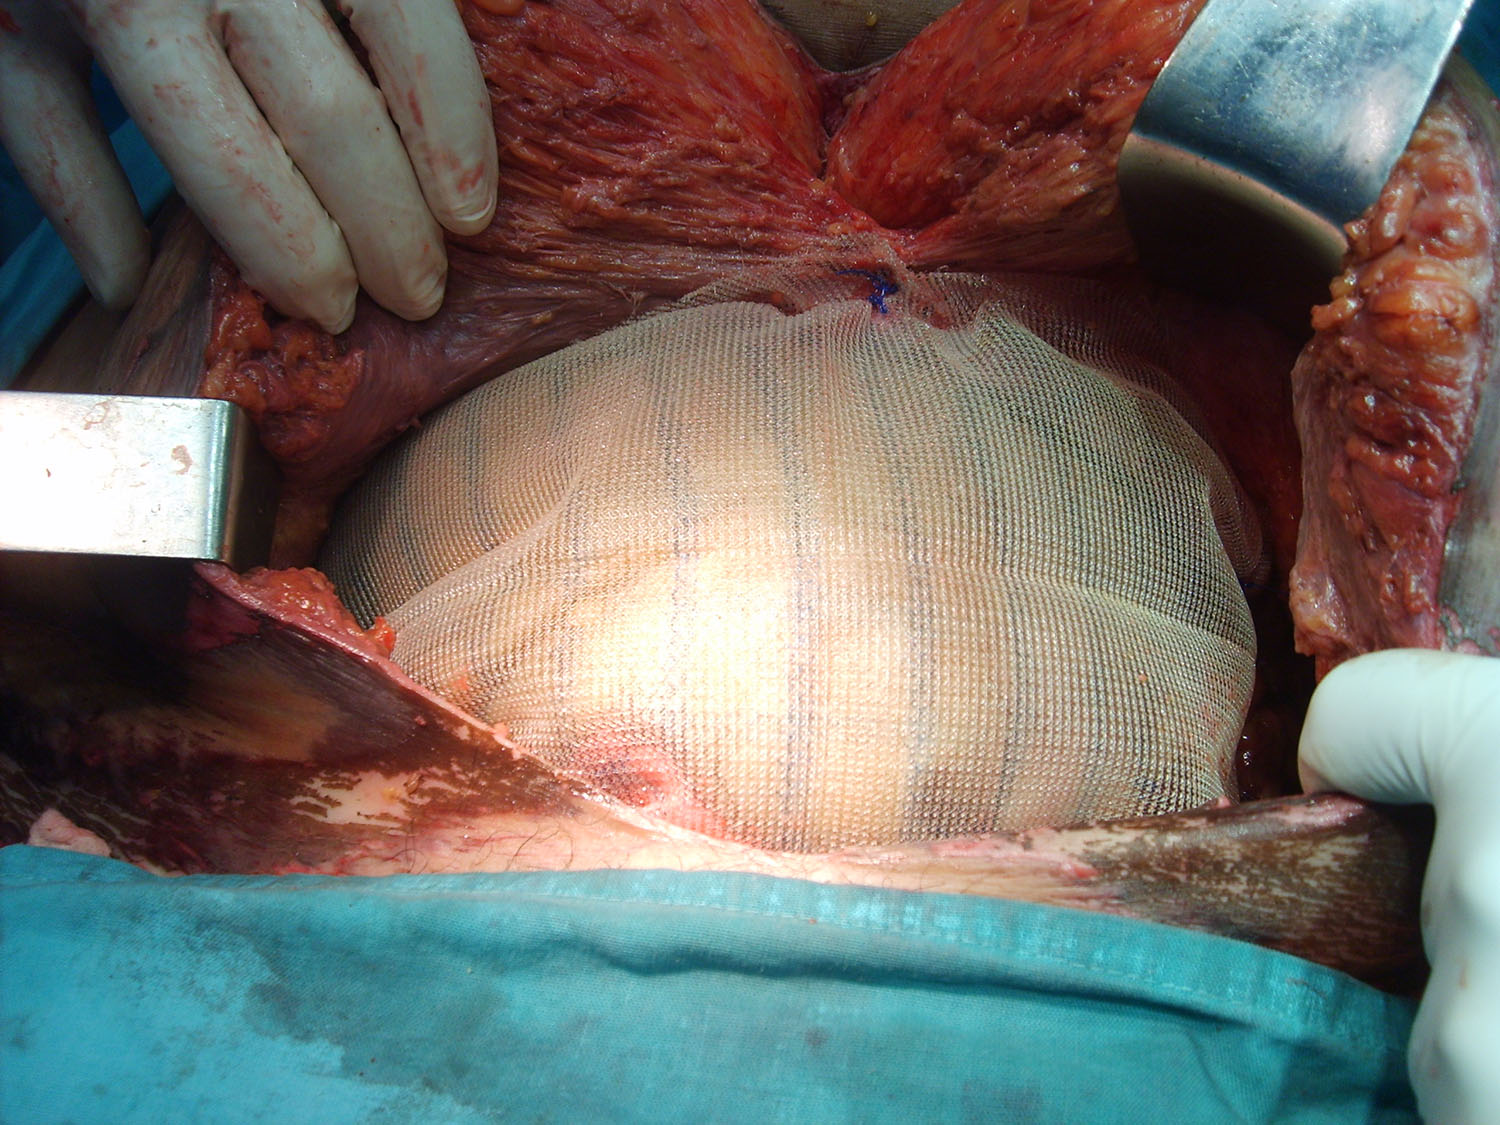

Luego de estabilizada la paciente y al cuarto día de la cirugía del abdomen abierto se lleva la paciente al quirófano. Se constata abdomen con escaso liquido serohemático y asas intestinales sin compromiso vascular por lo que se decide cerrar el abdomen. Es dificultosa la tarea de contener las asas intestinales en la cavidad abdominal debido a la ausencia de pared lateral. Se decide el decolamiento del colon derecho e izquierdo a fin de lograr un espacio para colocar la prótesis, es decir generar un espacio real con el peritoneo para introducir la malla. La sugerencia adecuada del Dr Zorraquino es imposible de realizar, la enferma presenta una retracción importante de los músculos rectos que determinan una cavidad abdominal que supera ampliamente los 900 cm². Se coloca dos mallas de proceed 30 x 30 intraperitoneal fijadas con puntos al espesos total de los remanentes musculares y sobre la misma una malla de prolene 30 x 30 fijada abajo al pubis y a ambas crestas ilíacas y por arriba al plano aponeurótico de los rectos y Oblicuo mayor. Se deja piel y celular abierto. Vuelve a Cuidados Intensivos.

Interesantísimo caso el que nos presenta el Dr. Carlos Cano, bien iconografíado. Se ve en la última foto o así lo interpreto la sección de los músculos rectos y oblicuos.

Estimado Dr Reyes, aprecio tus comentarios, nosotros no disponemos de mallas biológicas, que si creo hubiesen sido de utilidad en este caso.Con respecto a colocar malla de polipropileno sobre la proceed, fué para tratar de darle más contención al contenido abdominal, por eso esa prótesis la fijamos al pubis y a las crestas ilíacas que estaban totalmente a la vista, según mostramos en algunas fotos.